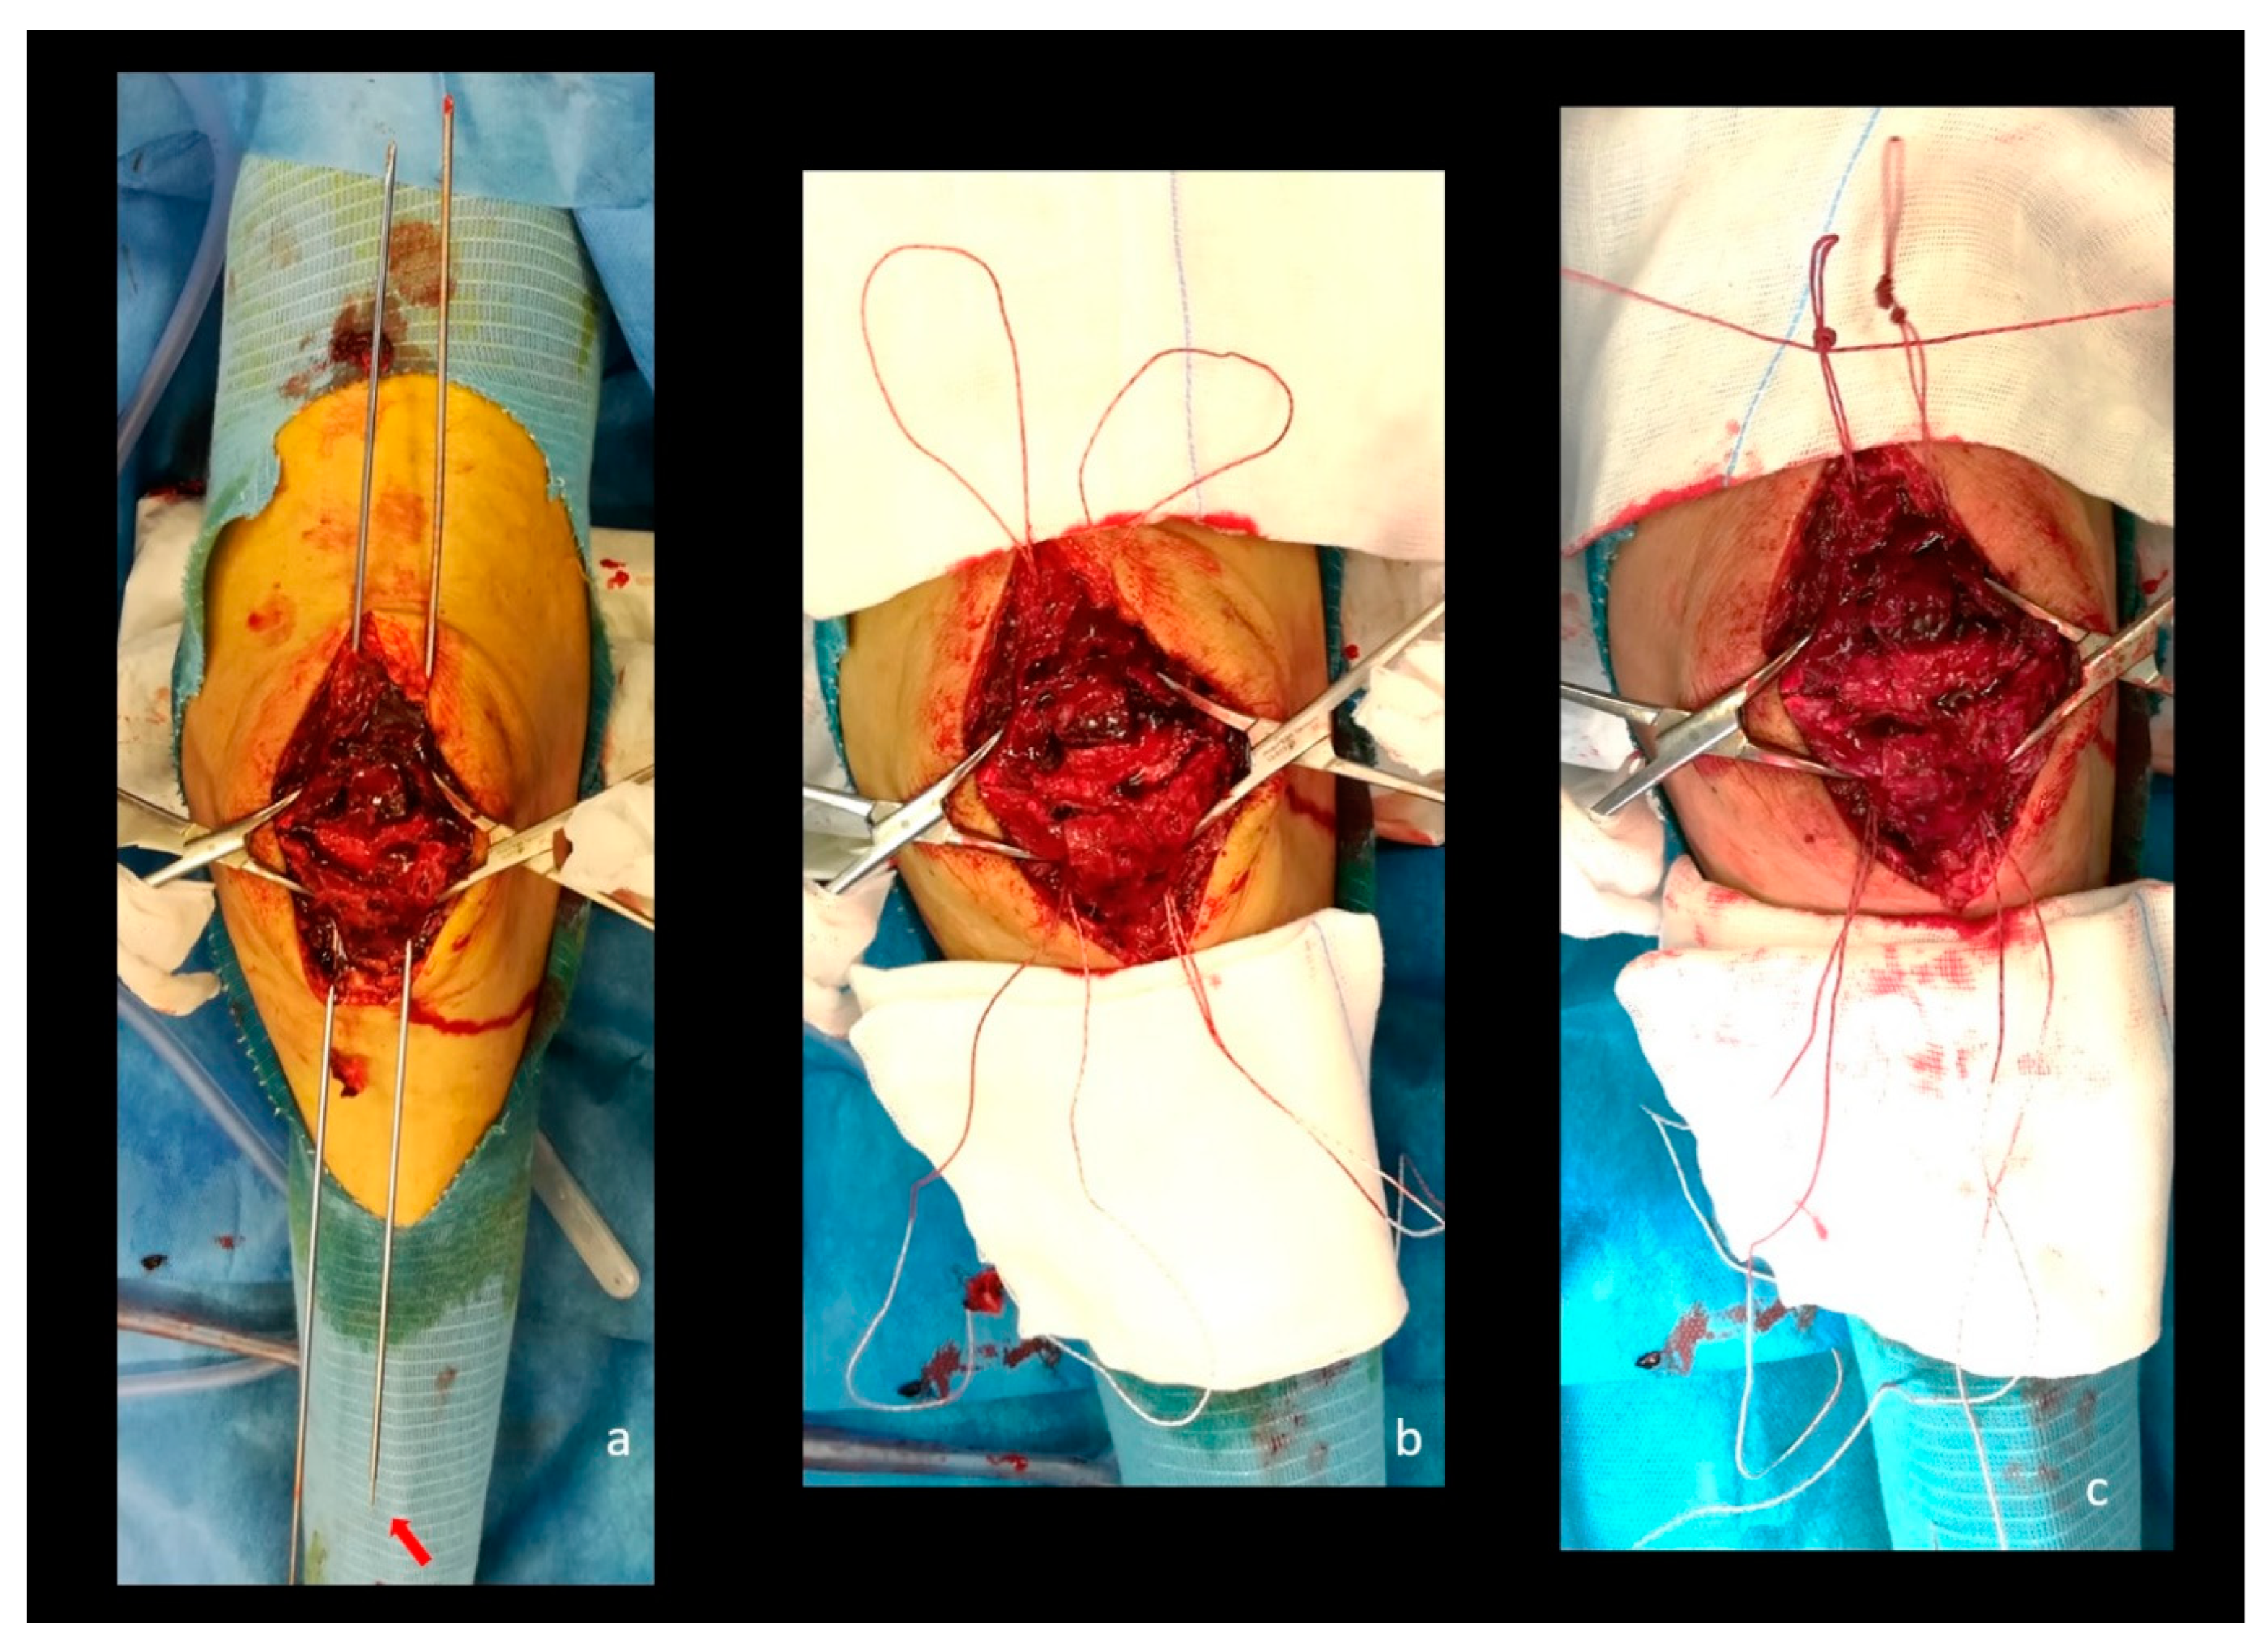

Clinical picture showing the phases described in the previous figure. (a) Two shuttle wires passing through the patella connected at the distal end with shuttle sutures attached to the looped FiberWire (red arrow); (b) No. 5 FiberWire sutures are passed through the patella with a loop on the upper pole; (c) a noose is created on the upper pole to prevent the lower migration of the FiberWire sutures. Note the third FiberWire passing through the inferior part of the nooses.